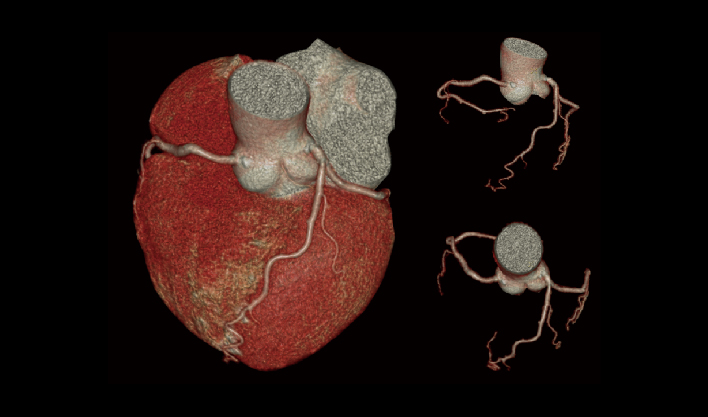

快速扫描,精准“冻结”器官运动瞬间,高清呈现亚毫米结构,为心血管等系统疾病早期诊断和治疗提供黄金窗。

一次屏气快速扫描

精准“冻结”运动瞬间

避免呼吸伪影